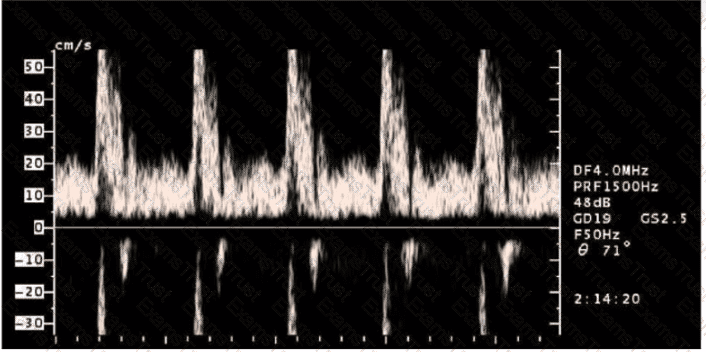

Question 28

Which pulsed-wave Doppler adjustment would be appropriate to correct the aliasing seen in this image?

Options:

A.

Increase the spectral Doppler gain.

B.

Decrease the spectral Doppler gain.

C.

Increase the Doppler pulse repetition frequency.

D.

Decrease the Doppler pulse repetition frequency.